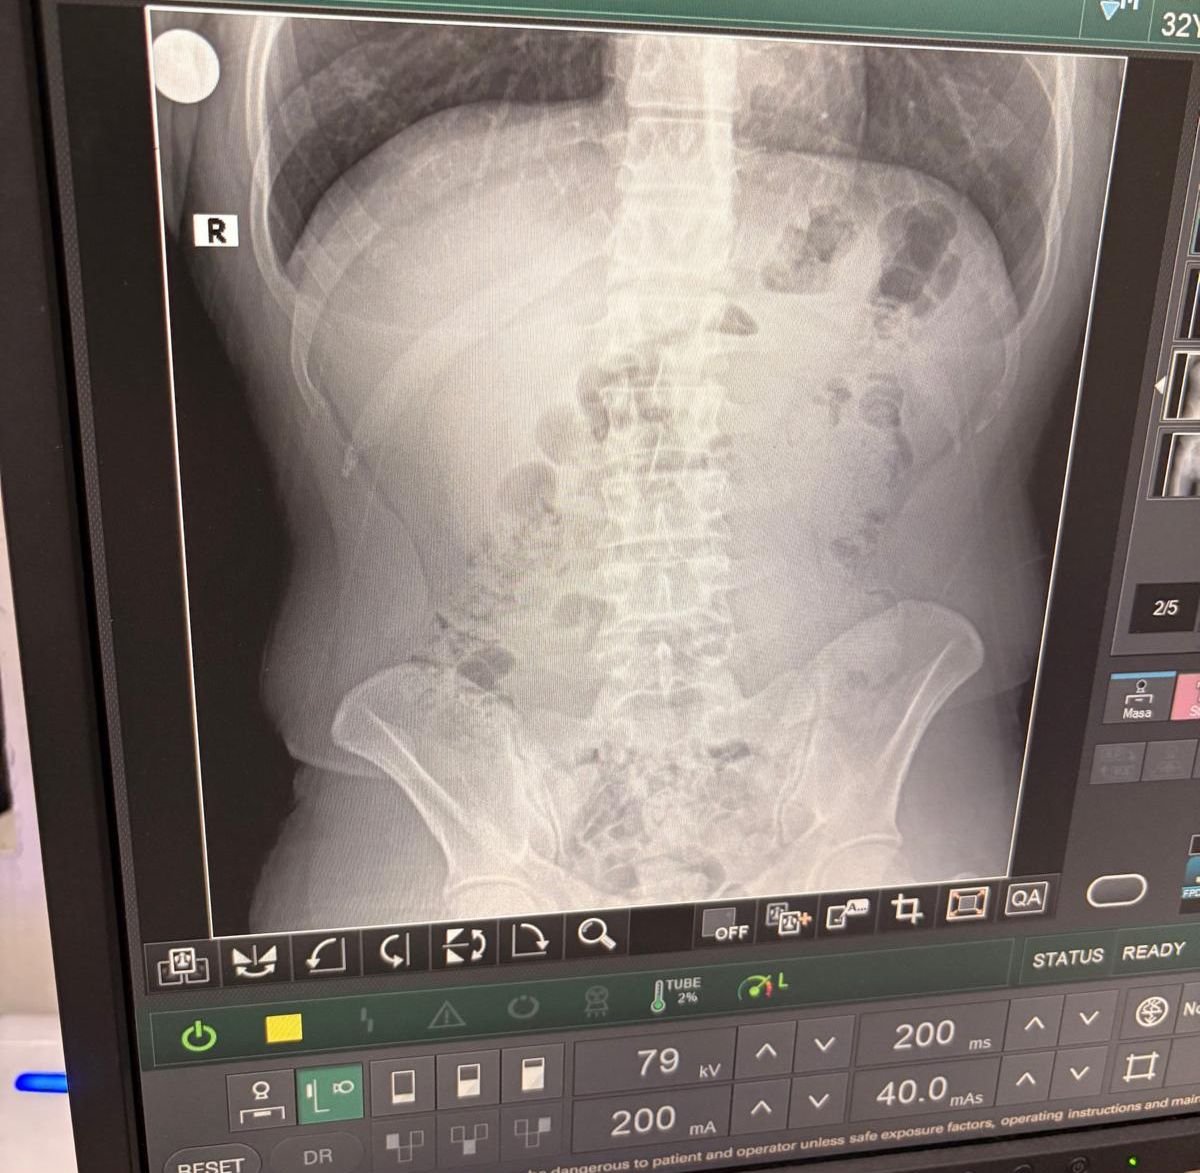

Uşak İl Emniyet Müdürlüğü Narkotik Şube ekipleri, kapsüller halinde paketlenen uyuşturucu ele geçirildi.140 kapsül halindeki uyuşturucu maddenin 1 kilo 516 gram geldiği ifade edildi. Uşak’taki narkotik ekipleri gözaltına aldıkları 3 yabancı uyruklu kişiyi, ifadesini aldıktan sonra adliyeye sevk etti. Burada ifadeleri bir kez daha alınan 3 kişi tutuklanarak cezaevine kondu.